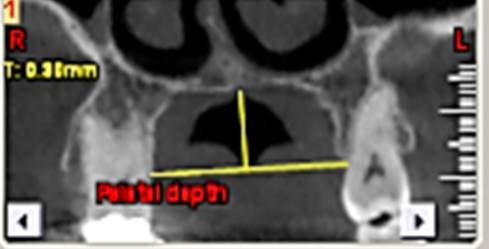

First, the radiographs were evaluated in relation to the endodontic and periodontal problems of the teeth and divided into 5 groups based on periapical index scoring, the periapical status was graded as follows: 1) normal periapical structures; 2) minor changes in bone structure; 3) some changes in bone structure with some loss of minerals; 4) periodontitis with a well-defined radiolucent area; and 5) severe periodontitis with exacerbating features.25 The patients’ genders were also recorded. In the next stage, the teeth were evaluated for the presence of periapical and periodontal lesions, followed by determination of the distance between the maxillary sinus floor and the nearest apex of the root of the first molar (Figure 1, A) and the nearest alveolar crest of the first molar on the buccal or lingual aspect (Figure 1, B). Furthermore, the buccopalatal thickness in the area superior to the apex of the first molar was determined in the coronal dimension (Figure 2). In the next stage, a line was drawn perpendicular to the line connecting the palatal crests of the first molars on both sides in order to measure the depth of the palate (Figure 3). Finally, the thickness of the schneiderian membrane was determined at three regions of the maxilla: medial, lateral and inferior. Then the mean of the 3 values was used as a reference (Figure 4).

Figure 3. the palatal depth